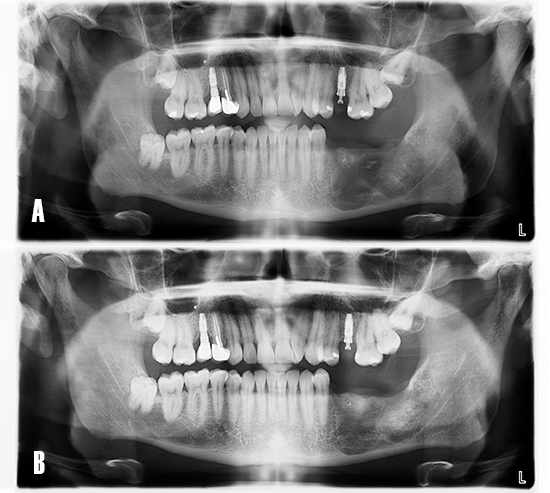

El caso fue evaluado a los 24 meses de carga funcional. El examen radiológico mostró un adecuado nivel del hueso marginal respecto al día de instalación de los implantes, así como la neoformación de la zona asociada a la patología quística (Fig. 15).

Figura 15. Ortopantomografía. A) Día de la colocación de implantes. B) A los 24 meses tras la carga funcional de los implantes.

El enfoque terapéutico descrito en el presente caso, permitió realizar la cirugía de implantes tras 12 meses de cicatrización. La ortopantomografía mostró cómo la zona tratada se torna más radiodensa, imagen compatible con neoformación ósea. Sin embargo, la TCHC mostró un defecto residual en la zona distal del implante en posición 3.7, por lo que se realizó una regeneración ósea simultánea con un biomaterial aloplástico particulado.

Los implantes osteointegraron de forma satisfactoria, y fueron sometidos a carga a las 16 semanas de tratamiento tras la confección de la restauración definitiva mediante técnica de escaneado intraoral. Los hallazgos clínicos y radiográficos durante el seguimiento mostraron que el enfoque terapéutico resultó ser predecible y satisfactorio.